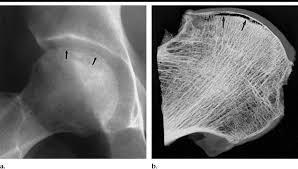

What is Crescent sign of the femur?

Subchondral lucency at the femoral head

Indicates imminent articular collapse requiring arthroplasty

Defines Stage III AVN of femoral head